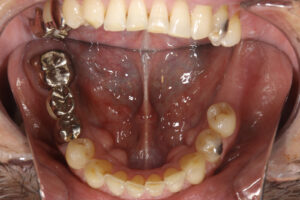

また、左下の欠損部にはインプラントを行うこととした。

- アングルクラスⅠであった。

- アングルクラスⅠで上下顎臼歯部に不適合な修復・補綴が見られ、

- クリーニングの後、上下顎臼歯部にセラミックインレー・アンレー・インプラントを装着した。

審美的な仕上がりで、患者自身も満足した。3年経過し良好である。

- 現在は2〜3ヶ月おきのメインテナンス中である。